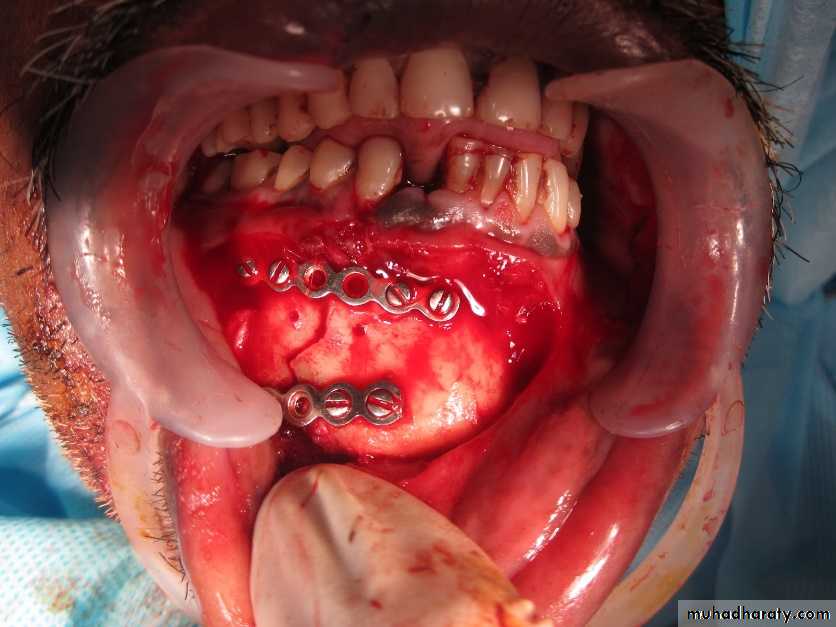

Methods of immobilization for fractures of the dentate mandible (Michael Perry 2015):a. Direct fixation (Osteosynthesis):- semi-rigid plates (manipulates)- Rigid plates (non-compression)- Compression plates- Lag screws- Resorbable plates and screws

c. External fixationd. Other methods (largely historical or where plates not available)- Trans-osseous wiring- Circumferential wiring- Transfixion (kirschner wires)1.e. in most circumstances open reduction and internal plate fixation(ORIF: Open Reduction and Internal Fixation) is now the main form oftreatment for mandibular fractures.

This method must not be used if the fracture is infected for the presence of metallic foreign body may cause bone necrosis and ulceration of the skin..Extra oral pin fixation:This method is rarely used because:1- May cause electrolytic action which may produce bone necrosis and2- The pin may project from the patient's jaw and may cause trauma and discomfort to the patient.Bone plating:The main advantage of bone plating is that it provides an extremely rigid fixation and therefore avoids unnecessary IMF at the conclusion of the operation and the patient can eat within few days after fixation.

(Rigid internal fixation is defined as: 'any form of fixation applied directly to the bones which is strong enough to prevent inter fragmentary motion across the fracture when actively using the skeletal satructure

The disadvantages of this method are:1. fracturing of the roots of the teeth2. metal fatigue fracture of the plate3. fracture of the small fragments of bone ends at the point of screw insertion4. scar5. infection and bone necrosis